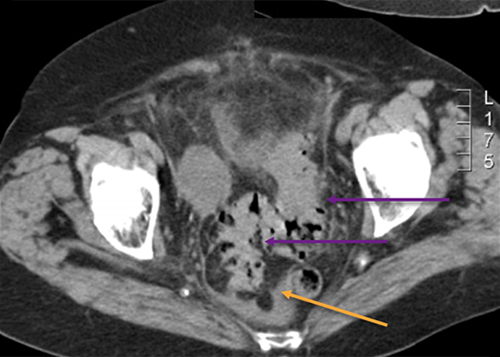

Monsieur A., 53 ans, est adressé aux urgences par son médecin traitant pour des douleurs abdominales fébriles. Celles-ci sont localisées en fosse iliaque gauche et hypogastre. Elles évoluent depuis quelques jours mais sont devenues plus intenses depuis vingt-quatre heures.

Cliniquement, il a une température à 38,2 °C, l’abdomen n’est pas distendu mais la palpation retrouve une franche douleur en fosse iliaque gauche et en hypogastre sans défense. Il n’y a pas de signe fonctionnel urinaire.

Le diagnostic est possible, il peut en effet donner des douleurs fébriles en fosse iliaque gauche, d’autant que le patient pratique des injections sous-cutanées d’insuline dans sa cuisse, ce qui peut être une porte d’entrée de l’infection.

Le diagnostic est tout à fait possible, à évoquer ici en première intention devant l’âge (> 40 ans) et la symptomatologie (douleurs fébriles en fosse iliaque gauche et hypogastre).

– de la localisation de la douleur en fosse iliaque gauche ;

– du syndrome inflammatoire : fièvre à 38,5 °C avec hyperleucocytose à la biologie ;

– de l’argument de fréquence de cette pathologie à cet âge (la prévalence des diverticules sigmoïdiens est de plus en plus importante avec l’âge, après 40 ans).